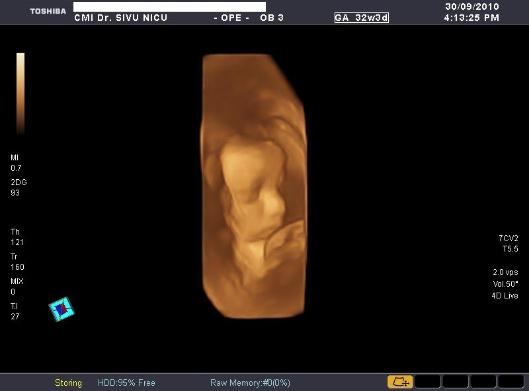

De sarcina (morfologie,biometrie,3D si 4D)

Poze realizate pe ecograful

Toshiba Applio XG